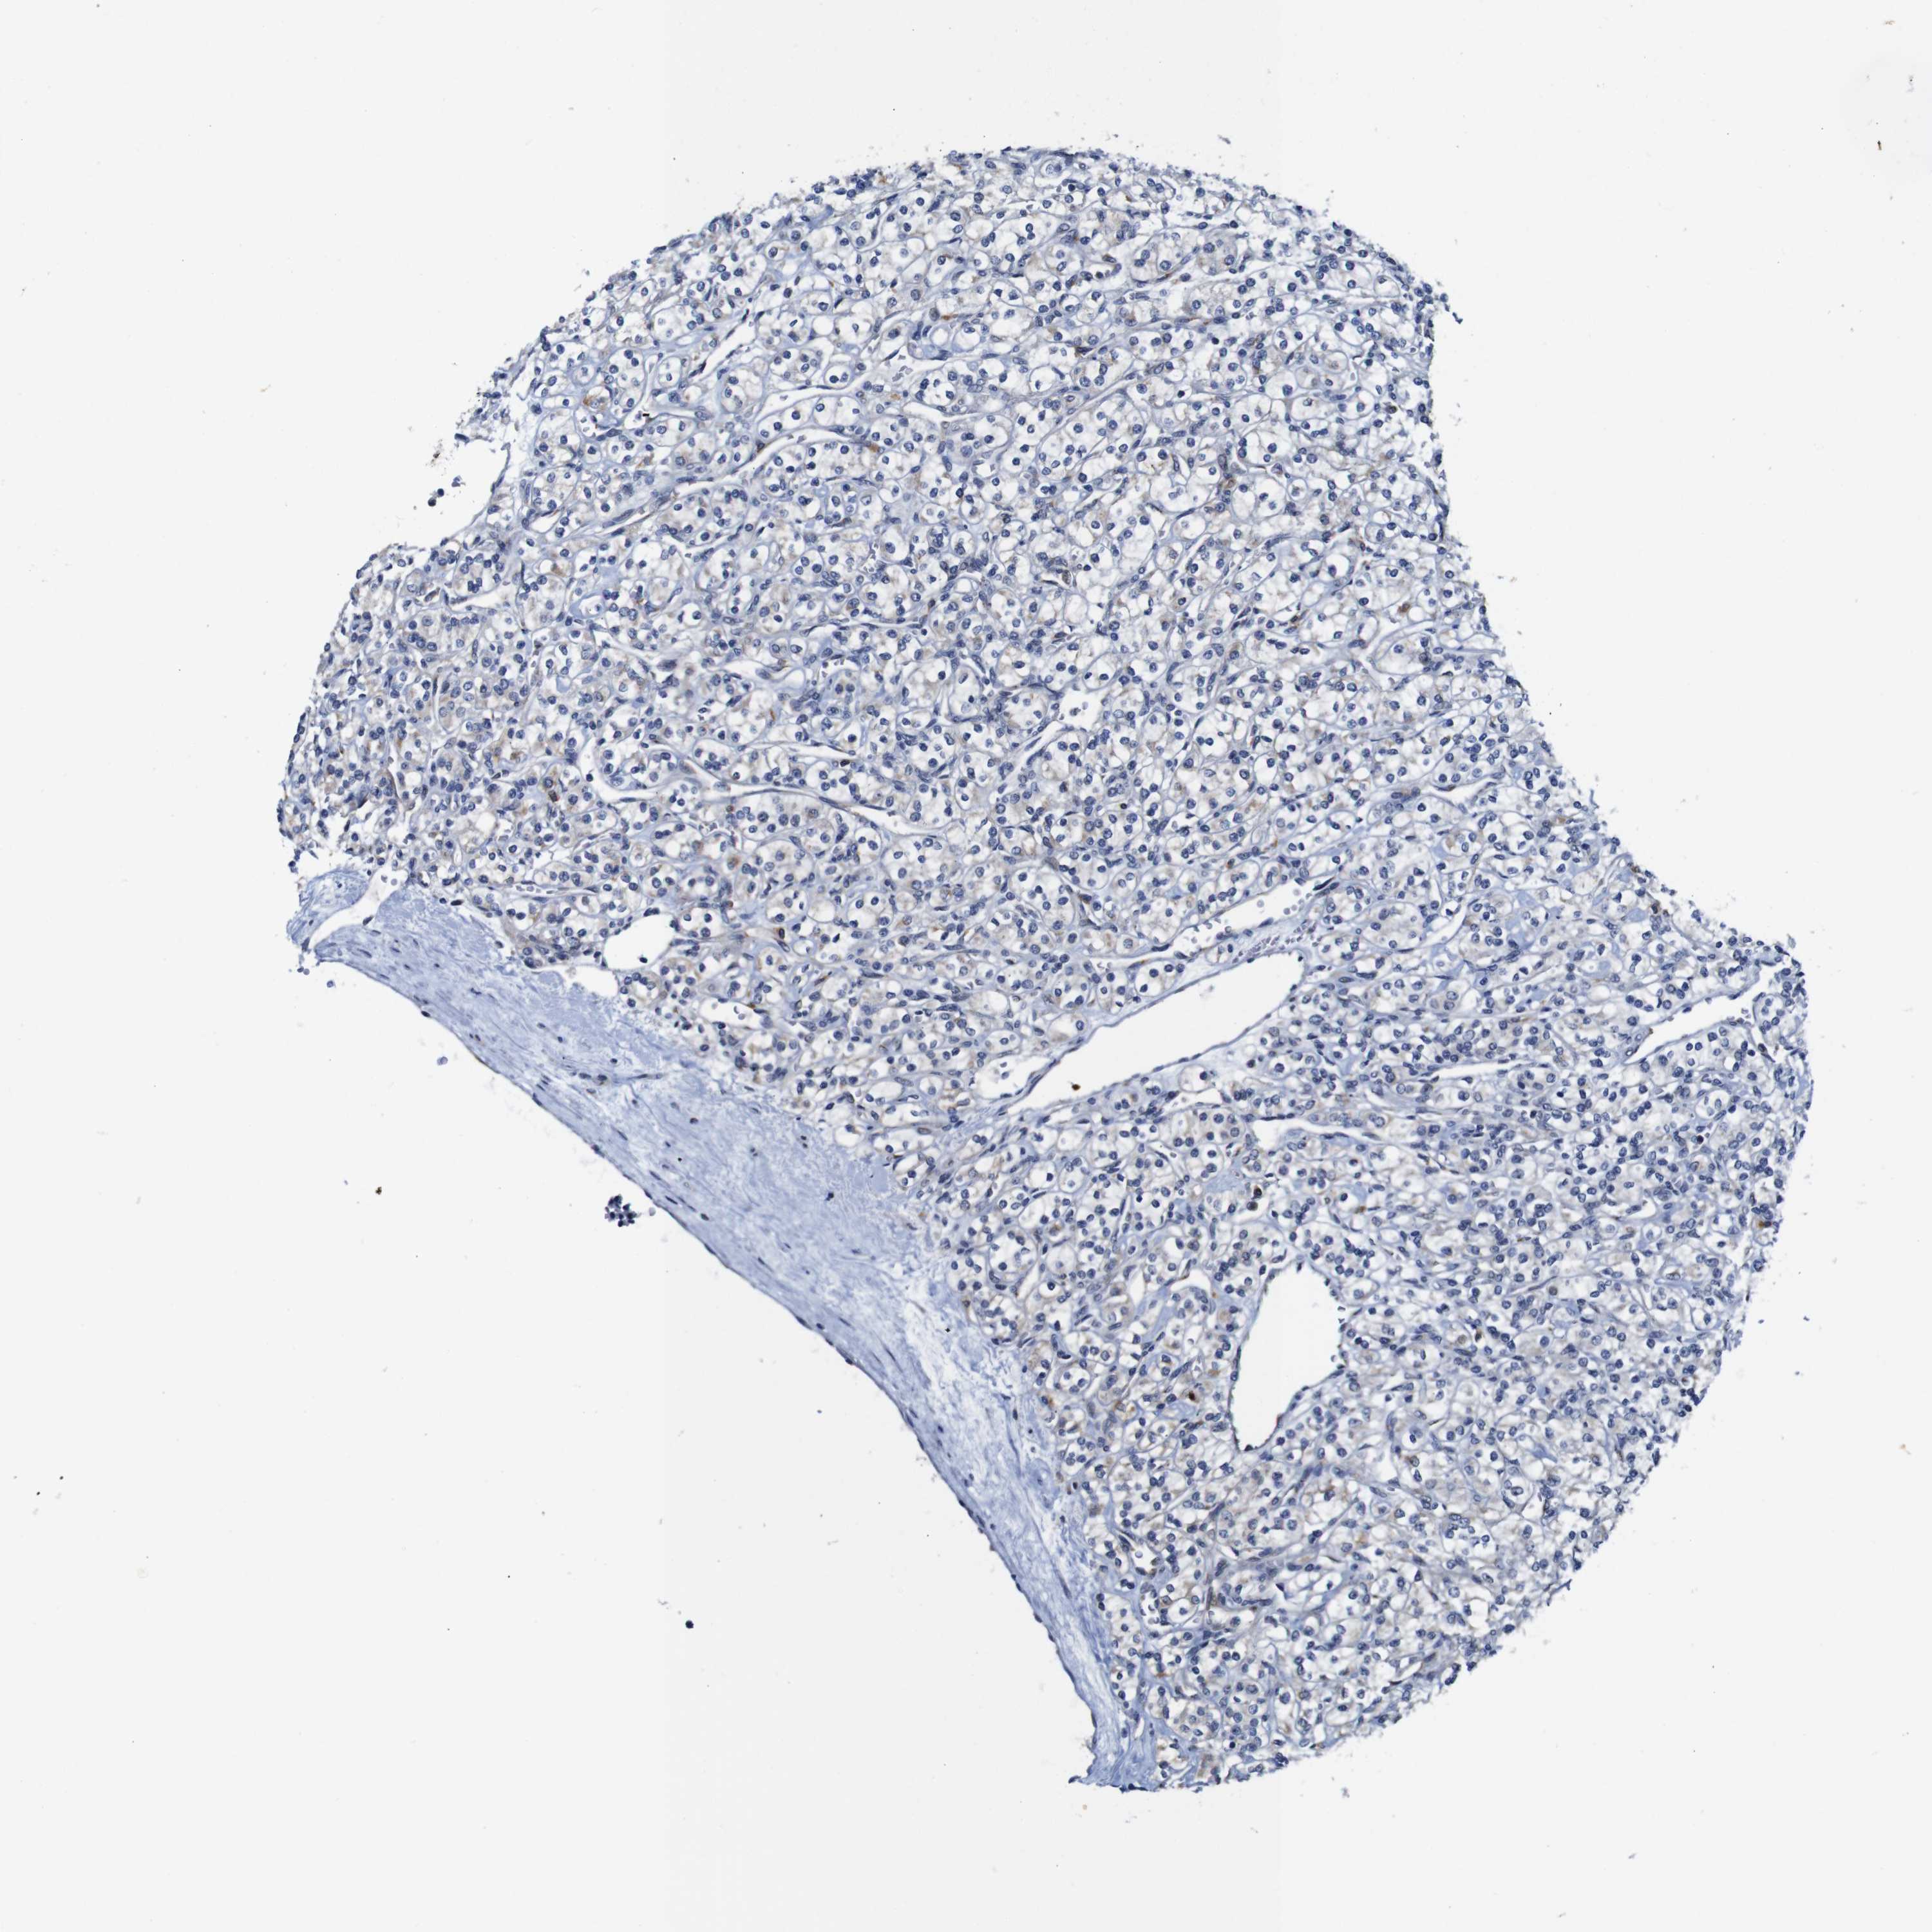

KIDNEY RENAL CLEAR CELL CARCINOMA (TCGA) - Interactive survival scatter ploti

The Survival Scatter plot shows the clinical status (i.e. dead or alive) for all individuals in the patient cohort, based on the same data that underlies the corresponding Kaplan-Meier plots. Patients that are alive at last time for follow-up are shown in blue and patients who have died during the study are shown in red.

The x-axis shows the expression levels (FPKM) of the investigated gene in the tumor tissue at the time of diagnosis. The y-axis shows the follow-up time after diagnosis (years). Both axes are complimented with kernel density curves demonstrating the data density over the axes. The top density plot shows the expression levels (FPKM) distribution among dead (red) and alive patients (blue). The right density plot shows the data density of the survived years of dead patients with high and low expression levels respectively, stratified using the cutoff indicated by the vertical dashed line through the Survival Scatter plot. This cutoff is automatically defined based on the FPKM cutoff that minimizes the p-score. The cutoff can be changed by dragging the vertical line or by entering a cutoff value in the square labeled "Current cut-off".

Under the Survival Scatter plot the p-score landscape (black curve; left axis) is shown together with dead median separation (red curve; right axis). Dead median separation is the difference in median mRNA expression between patients who have died with high and low expression, respectively. It is calculated as follows: median FPKM expression of dead patients with high expression - median FPKM expression of dead patients with low expression. This is intended to aid the user in visually exploring custom cutoffs and the associated p-scores and dead median separation.

Individual patient data is displayed and can be filtered by clicking on one or more of the category buttons on the top of the page. Categories describing expression level and patient information include: high, low, alive, dead, female, male and tumor stages. The scale of the x-axis can be toggled between linear and log-scale by clicking on the "x log" button. Mouse-over function shows TCGA ID, patient information and mRNA expression (FPKM) for each patient.

& Survival analysisi

Kaplan-Meier plots summarize results from analysis of correlation between mRNA expression level and patient survival. Patients were divided based on level of expression into one of the two groups "low" (under cut off) or "high" (over cut off). X-axis shows time for survival (years) and y-axis shows the probability of survival, where 1.0 corresponds to 100 percent.

FURIN is potential prognostic, high expression is favorable in Kidney Renal Clear Cell Carcinoma (TCGA)

Best expression cut offi

Based on the FPKM value of each gene, patients were classified into two groups and association between prognosis (survival) and gene expression (FPKM) was examined. The best expression cut-off refers the FPKM value that yields maximal difference with regard to survival between the two groups at the lowest log-rank P-value. Best expression cut-off was selected based on survival analysis .

When clicking on this number, the vertical dashed line indicating cut-off, the interactive survival plot, and the Kaplan-Meier curve will be adjusted to show results based on the best expression cut-off.

: 28.29

TCGA RNA samplesi

RNA-seq data is reported as average FPKM (number Fragments Per Kilobase of exon per Million reads), generated by the The Cancer Genome Atlas (TCGA) .

Normal distribution across the dataset is visualized with box plots, shown as median and 25th and 75th percentiles. Points are displayed as outliers if they are above or below 1.5 times the interquartile range. FPKM values of the individual samples are presented next to the box plot.

Average pTPM 37.4

Number of samples 521